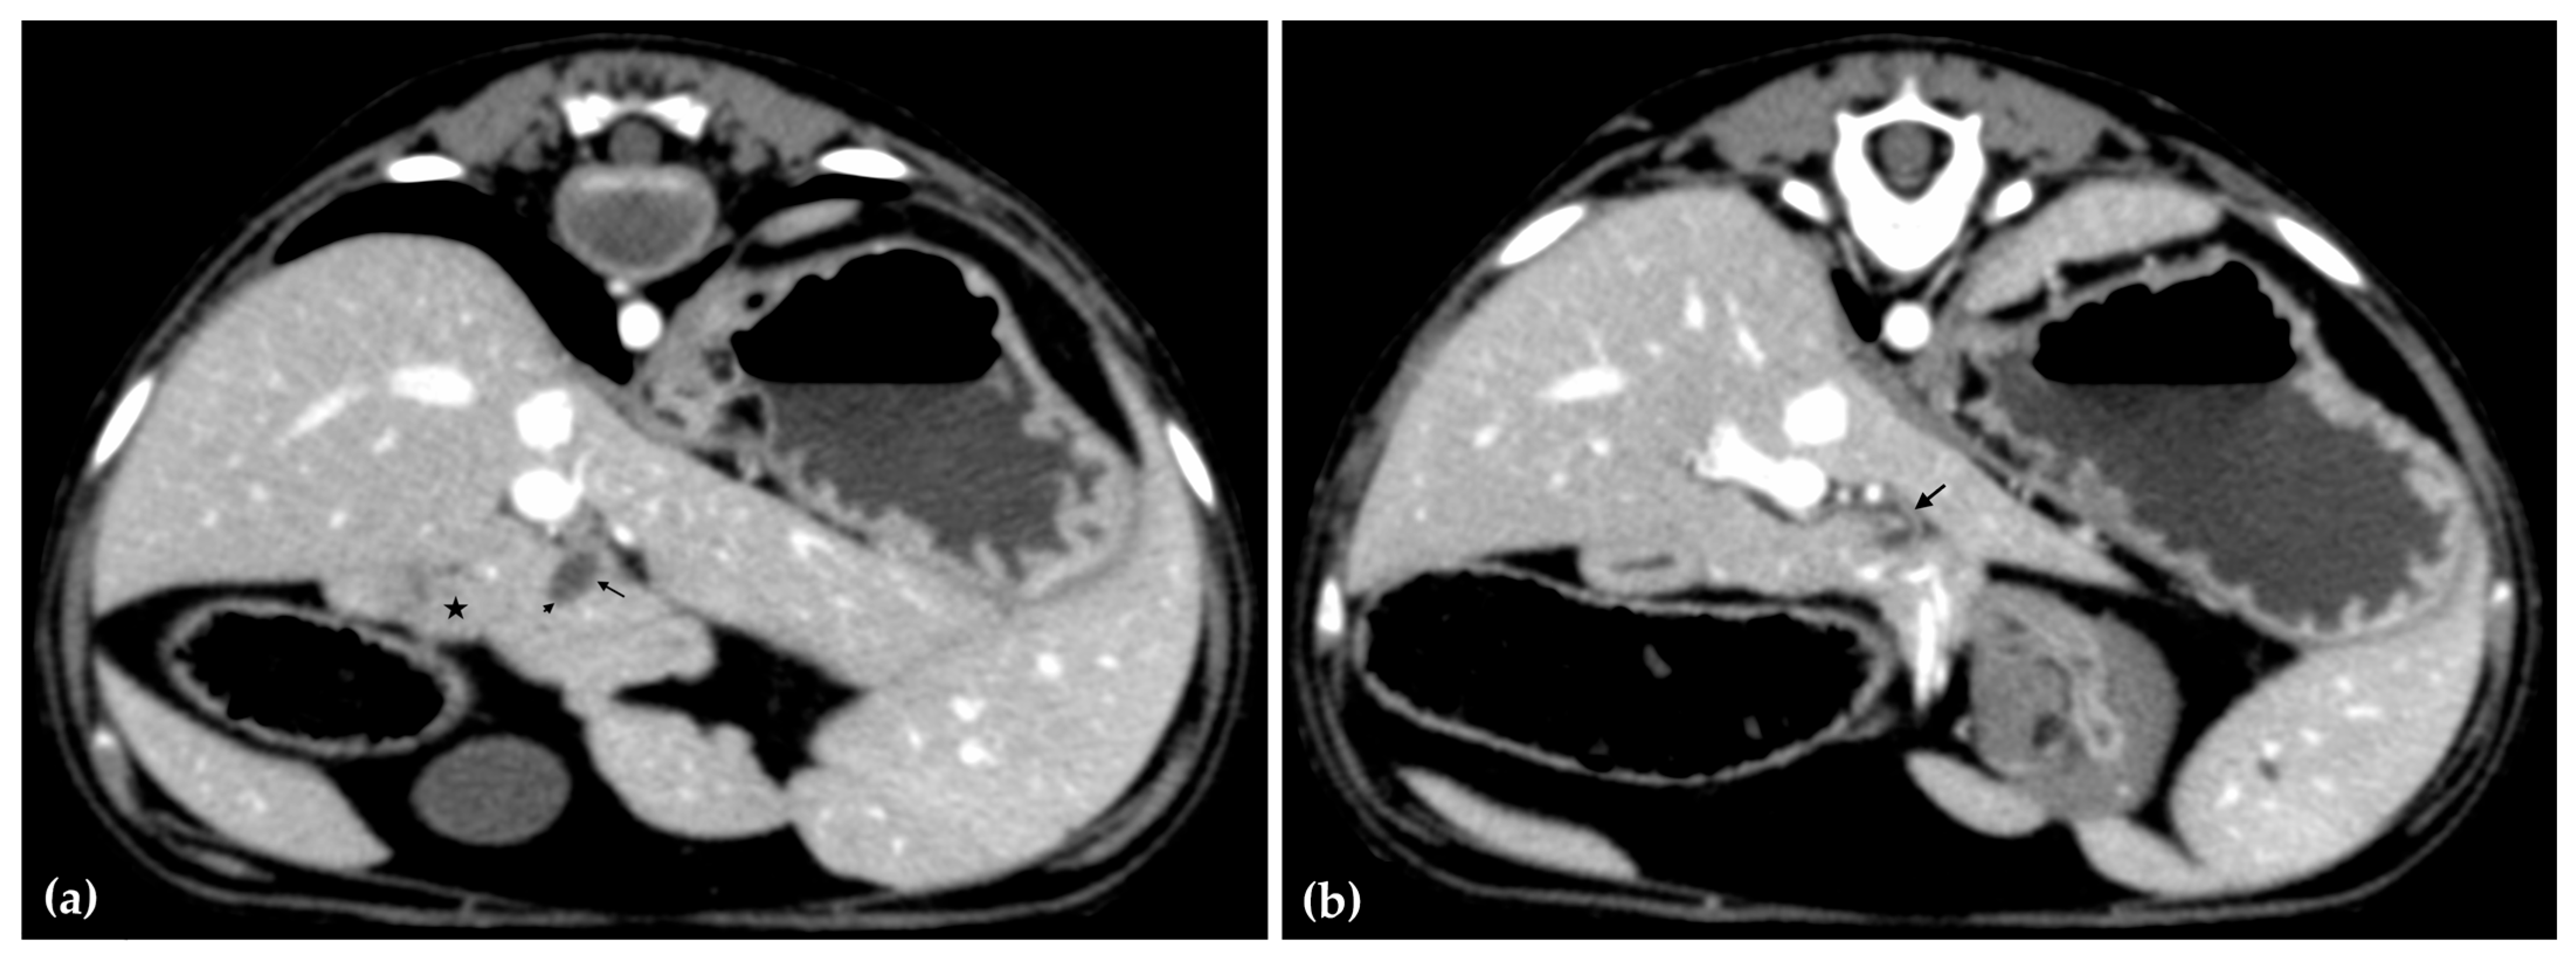

Abdominal radiographs showed no significant abnormalities except a large amount of fecal material in the large intestine. The patient was placed in dorsal recumbency for an abdominal ultrasound (microconvex and linear probes 12–18 MHz, Epiq 5G, Philips Ultrasound, Bothell, WA, USA), with the ventrum shaved from above the xiphoid to the pubis in a roughly square-shaped region. Ultrasound coupling gel and alcohol were used for image optimization. The gallbladder was moderately filled with anechoic fluid and the cystic duct appropriately tapered to the common bile duct (CBD). The CBD could not be traced in its entirety, but the more distal identified segments were multifocally dilated, measuring up to 0.6 cm in diameter (outer wall to outer wall; Figure 1a). At its distal-most aspect, as it approached the duodenal papilla, the CBD abruptly tapered without a discrete intraluminal or extraluminal cause (Figure 1b). Several intrahepatic biliary ducts within the left liver hemisphere were distended distally, measuring up to 0.5 cm in dilation (inner wall to inner wall; Figure 2a,b). No intrahepatic biliary duct dilation of the right hepatic hemisphere was noted. Due to a concern for an unidentified biliary duct obstruction contributing to the patient’s clinical signs/changes, a dual phase contrast abdominal computed tomographic (CT) study was pursued for further evaluation.

Figure 1.

Ultrasound images of the liver. A portion of the common bile duct (CBD) is moderately-markedly distended (between + calipers) (a). Ultrasound image of the duodenum (black-rimmed white star), common bile duct (white arrowhead), and pancreas (blue-rimmed white circle). The distal common bile duct at the level of the duodenal papilla with abrupt narrowing (between calipers) (b).